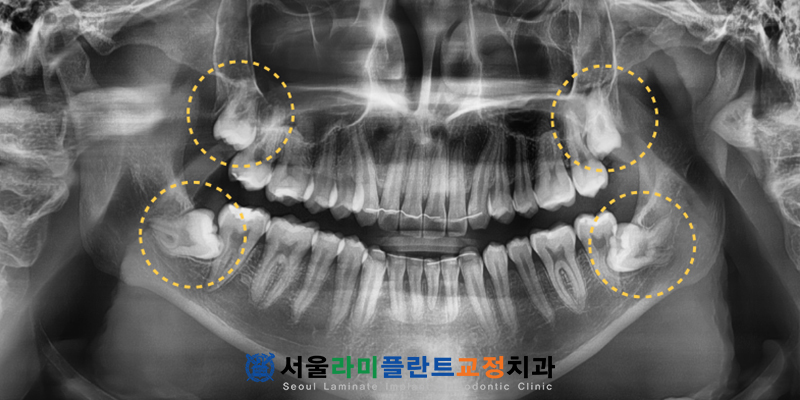

최근 동탄치과를 찾아주신

이십 대 초반의 남성 환자분께서는

치아 교정 치료를 모두 마치고

마지막 단계로 아래턱

매복 사랑니 발치를 앞두고 계셨습니다.

동탄치과 환자분께서는

곧 군 입대를 앞두고 있어

불편함을 미리 없애고자

매복된 사랑니 네 개를 동시에

발치하기를 희망하셨습니다.

하지만 정밀 검사 결과

오른쪽 아래에 위치한 사랑니의

상태가 매우 까다로웠습니다.

해당 치아는 잇몸 속에 깊이

매복되어 있을 뿐만 아니라

치아의 뿌리가 심하게

휘어져 있는 형태였습니다.

무엇보다 큰 문제는 사랑니의 뿌리가

아래턱 신경관인 하치조신경관과

겹쳐 보일 정도로 매우 가깝게

인접해 있다는 점이었습니다.